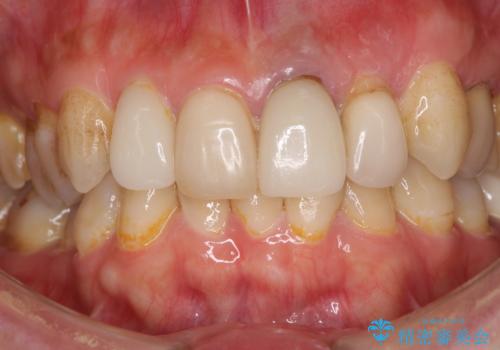

歯肉移植を用いた前歯のオールセラミックブリッジ

- 前歯が折れてしまい、ブリッジによる補綴治療を希望して来院された患者様です。

折れている前歯は抜歯をし、痩せてしまう歯肉は移植術により増大させることで審美面を回復した後、オールセラミックブリッジにて補綴することとしました。

インプラントかブリッジか悩むところでしたが、既に治療されている前歯のクラウン周りの変色が気になっていたため、ブリッジにより色調を合わせたオールセラミックを装着することを選択しました。

歯肉ラインや歯の形態、色調を整えることができ、患者様には大変満足していただきました。